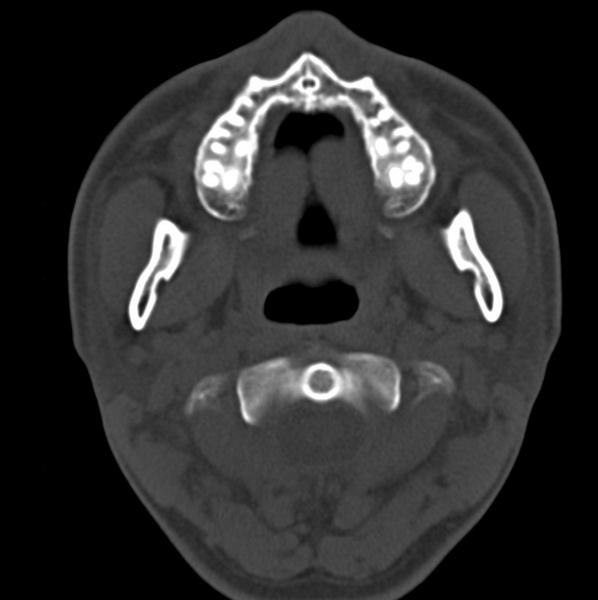

男、31、鼻咽部肿瘤放疗后请帮忙看看。

效果好,右侧破裂孔扩大,局部骨质缺损,为颅底骨质破坏。

1)鼻咽部肿瘤侵犯颅底放疗术后改变。2)左侧蝶窦炎。

咽后壁增厚,左侧咽鼓管隆突增大、咽鼓管咽口变浅,同侧咽旁间隙较窄。右侧颅底骨质破坏?为什么不在同一侧?

鼻咽部肿瘤侵犯颅底放疗术后改变.